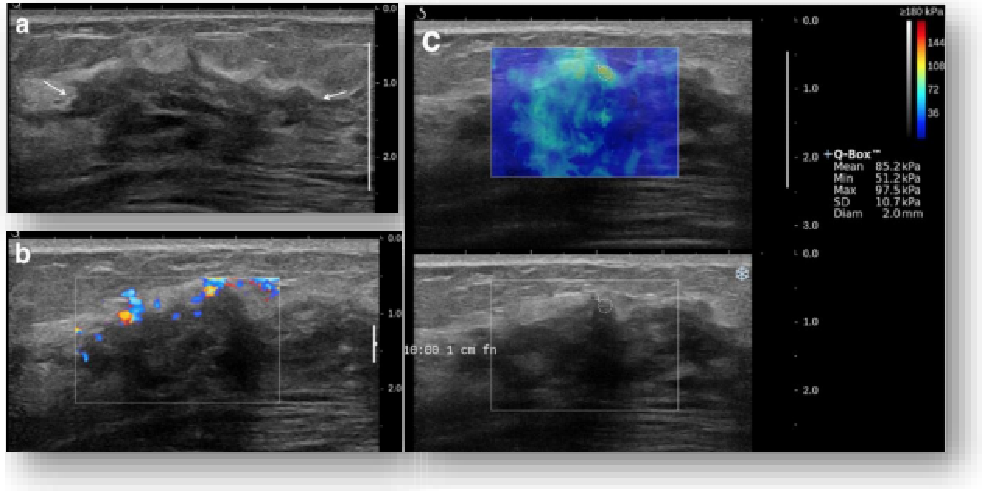

实时剪切波弹性成像

评估组织的软硬,并且提供定量数值,从而提示组织的良恶性。

鉴别诊断、精准分级、定量评价、穿刺引导、疗效评估、随访观察

image.png

恶性占位常常向周边组织进行侵润及扩散,二维很难观察到浸润部分的边界。使用实时剪切波成像能够对占位及周边组织进行硬度评估,通过颜色编码来区分不同组织的硬度信息,直观的观察占位组织的边界信息,更方便区分占位组织和正常组织的边界,准确评估消融范围。

左图病例所示:

钼靶阴性,B型发现非肿块病变

剪切波弹性成像见明确的硬度增高区域。

穿刺及手术病理结果:浸润性导管癌(IDC)

非肿块型病变:B型图像无法确认病变范围,E成像帮助发现异常区域和评估